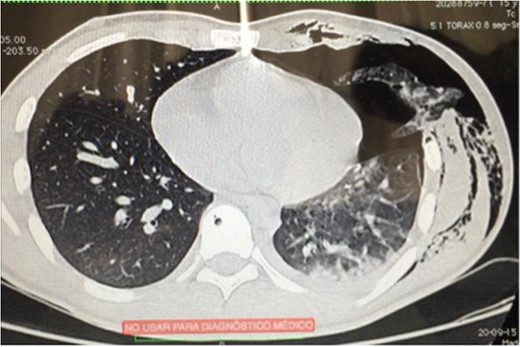

The chest CT showed moderate hemothorax, pneumothorax, a displaced fracture of the fifth left rib, and protrusion of a lung segment through a chest wall defect (Fig. 1).